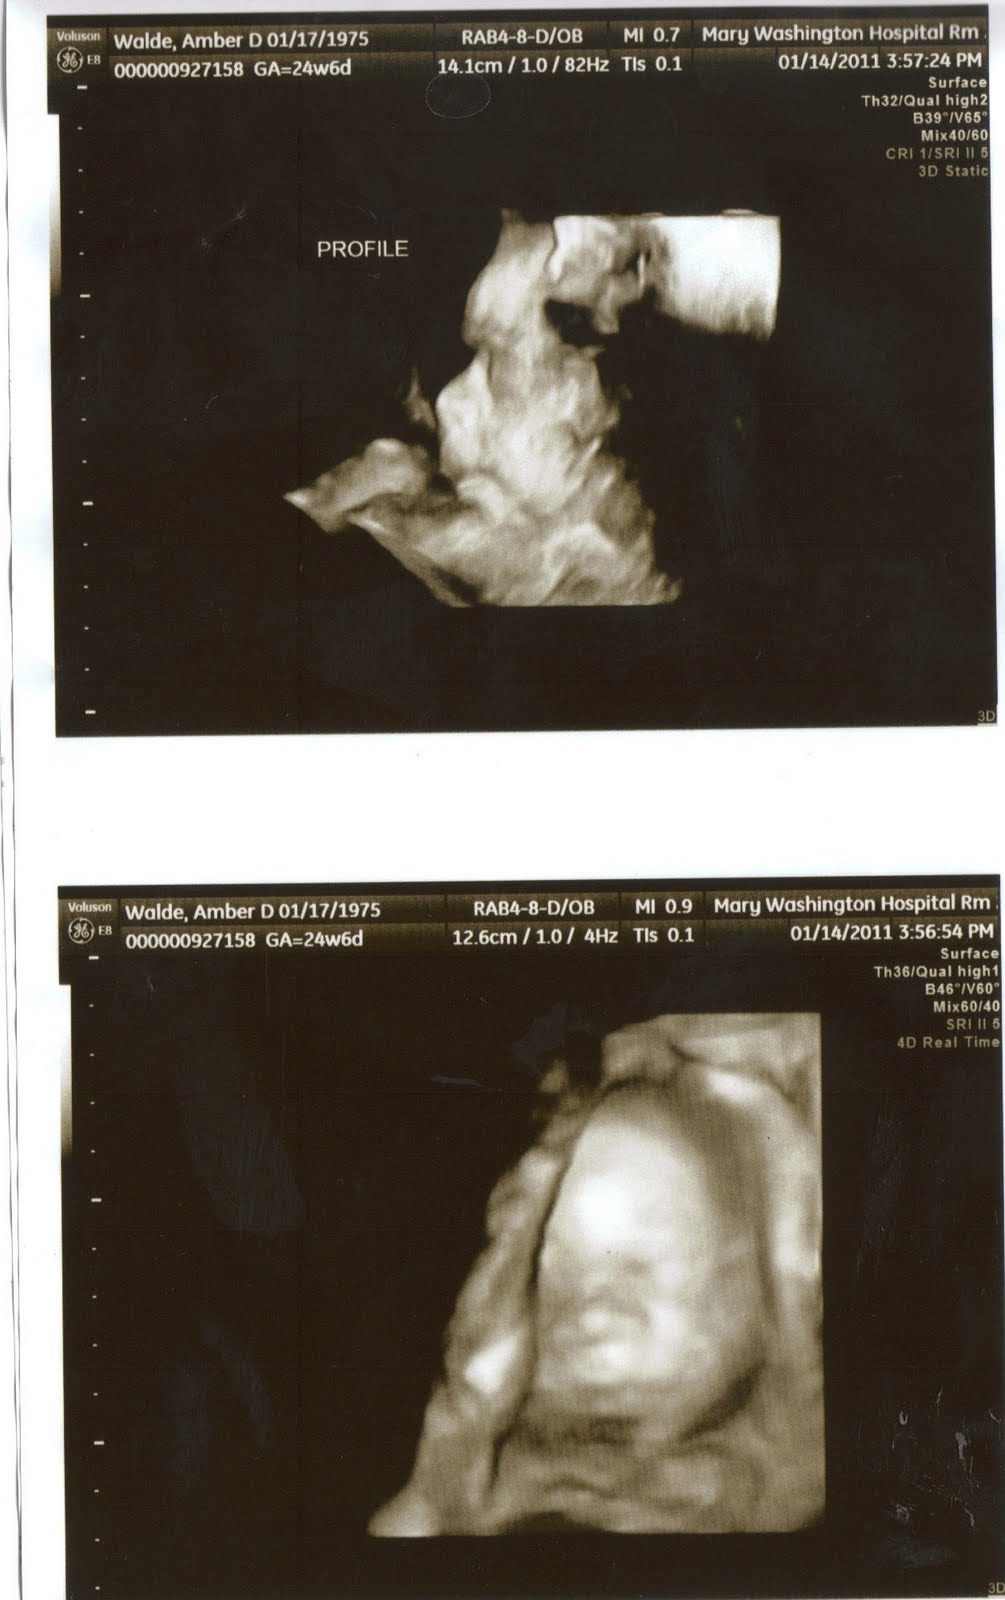

Look below for the latest baby boy pics.

A 3D pic of his face, and below that his profile

A 3D pic of his profile, and below that another (better) 3D pic of his face